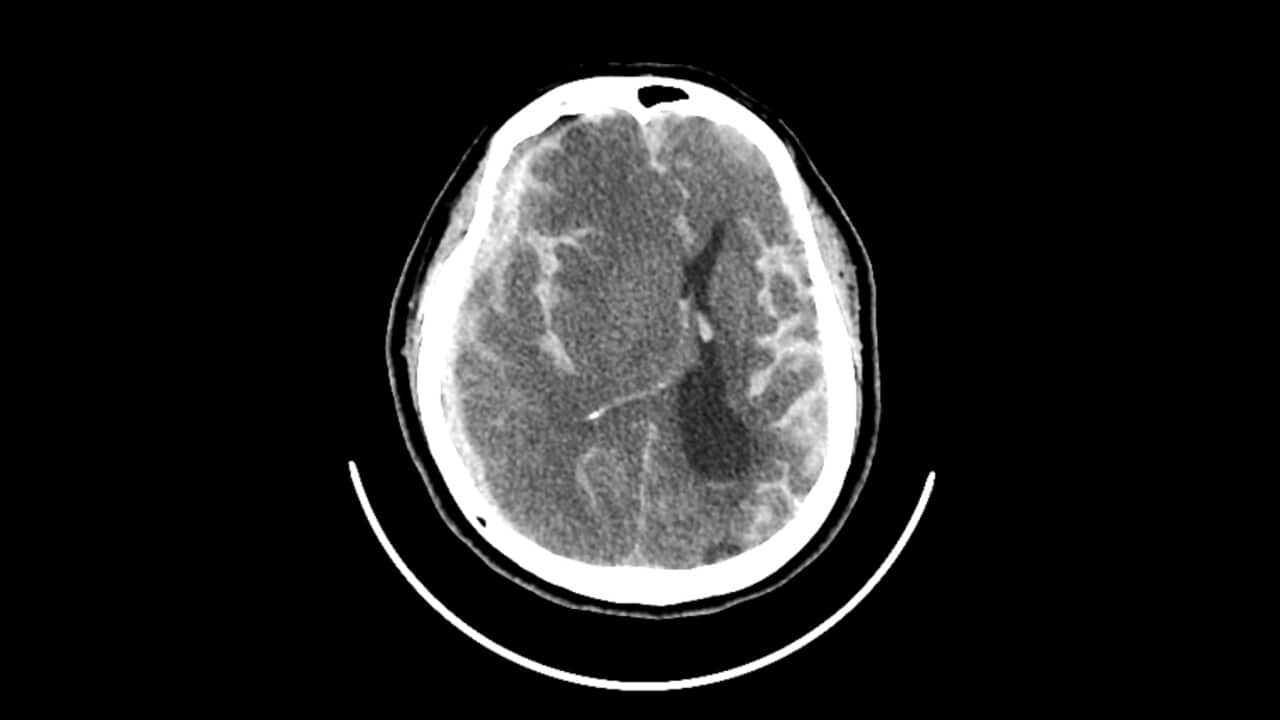

Stroke adalah penyebab kecacatan nomor satu di Australia, dengan satu dari empat orang diperkirakan akan mengalami stroke selama hidup mereka.